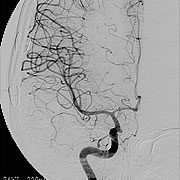

術中脳血管撮影

治療困難な大型動脈瘤や深部にある動脈瘤では顕微鏡観察だけでは完全なクリッピングができているのか、或いは動脈瘤の親血管が狭くなっていないかといった検討が十分にできないことがあります。そこで当科では術中血管撮影を行い、完全なクリッピングと、親血管の血流が保たれていることを手術中に確認し、手術の確実性、安全性を向上させています。

当科では放射線治療班と症例検討を行い、個々の患者さんに最も適切は治療を提供しています。 脳動静脈奇形の手術では、術中脳血管撮影を常に行い、全摘出を確認しています。また場合によっては脳動脈瘤手術同様に電気生理学的モニタリングも併用し、確実、安全な手術を行っています(図7、8)。